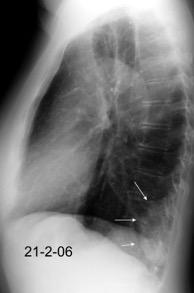

En relación con trasudados tabicados. Insuficiencia cardiaca

Hipoalbuminemia

Cirrosis / Fallo renal.

Operado aneurisma (prótesis). Líquido tabicado en cisuras

Fernandes de Paula MC et al. Focal pleural tumorlike conditions: Nodules and masses beyond mesotheliomas and metastasis. Respiratory Medicine 2015.

Derrame pleural “encapsulado”

“Tumor fantasma”

Asociado a fallo cardiaco. ( “Pleuritis adhesiva”). Buch KP. Chest. 2000